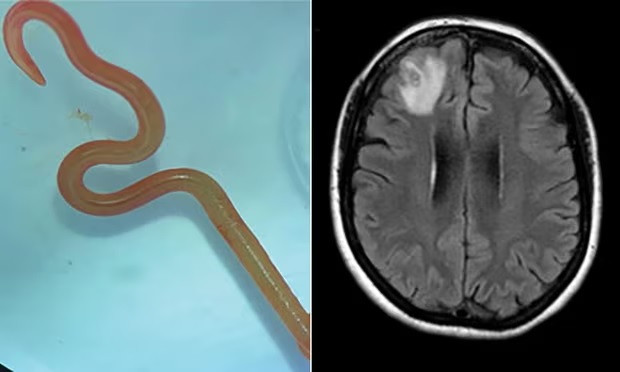

Australia: Phát hiện giun tròn sống ký sinh trong não người ảnh 1Loài giun vừa được phát hiện có tên Ophidascaris robertsi. (Nguồn: Guardian)

Các bác sỹ Australia vừa tìm thấy một con giun dài 8cm, sống ký sinh bên trong não của nữ bệnh nhân 64 tuổi, khi lấy ra vẫn còn sống.

Đây là loài giun có tên Ophidascaris robertsi, mà các nhà nghiên cứu cho biết là loài ký sinh trùng phổ biến ở chuột túi và trăn thảm (Carpet Python) - nhưng không phải ở người.

Đến năm 2022, sau khi bà bắt đầu mắc chứng đãng trí và trầm cảm, một bác sỹ phẫu thuật thần kinh ở bệnh viện Canberra nhận thấy sự bất thường ở thùy trán bên phải của não qua kết quả chụp cộng hưởng từ (MRI).

Bác sỹ thần kinh sau đó đã bàng hoàng khi phát hiện con giun tròn ký sinh và quyết định phẫu thuật. Hiện người phụ nữ vẫn đang được các chuyên gia tiếp tục theo dõi.